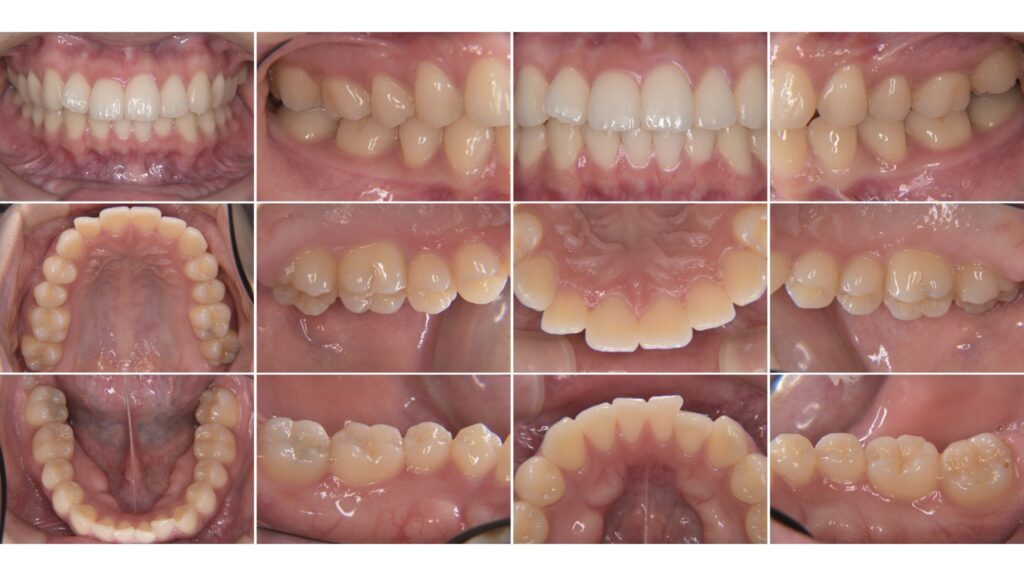

そこで当院では、口腔内写真を撮影し、現状を“見える化”しています。

口腔内写真を見ると、次のようなことがわかります。

• むし歯があるかどうか

• 以前治療した詰め物・被せ物の状態

• 歯ぐきが腫れていないか、下がっていないか

• 汚れがたまりやすい場所

• 磨き残しのクセ

• 歯の欠けやすり減り

• 噛み合わせによる歯への負担

• 奥歯や見えにくい部分の状態

• 今は症状がなくても、将来問題になりそうなところ

言葉だけの説明より、写真を見た方が一目で理解できます。